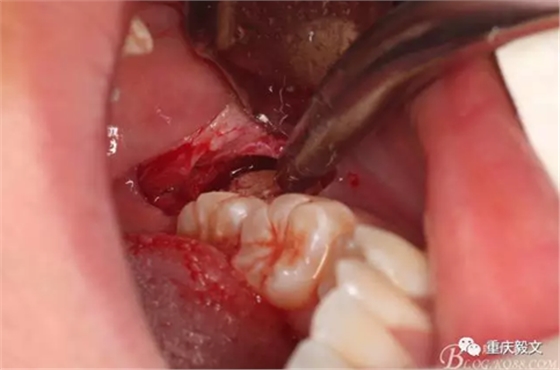

圖5切開(kāi)、翻瓣、去骨、暴露38牙冠。翻瓣從兩個(gè)切口的交接處開(kāi)始。掀起的瓣是全厚瓣。

圖6.去骨要點(diǎn):去除骨組織阻力。視牙齒周?chē)亲枇Φ亩嗌俣ㄈス橇?,以暴露牙齒的外形高點(diǎn)線(xiàn)為宜。高速牙鉆去骨,以頰側(cè)去骨為主,遠(yuǎn)中可少量去骨。舌側(cè)禁止去骨。